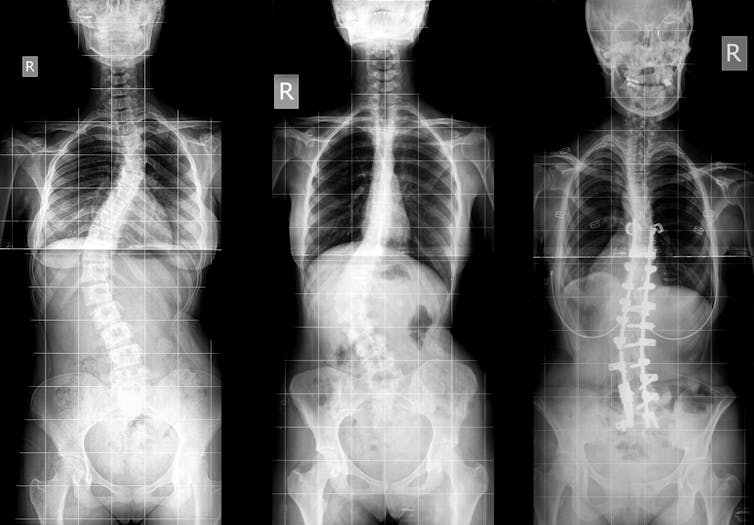

Some other form of deformity that may happen within the spinal column impacts no longer simplest the way it bends ahead and backwards, but additionally side-to-side.

Scoliosis happens when the vertebrae both curve sideways, rotate on the subject of each and every different, or cave in. This produces plenty of other deformities, ranging in measurement and severity.

Scoliosis impacts the spinal column.

martin81/ Shutterstock

In addition to again ache, sufferers might also realize postural indicators as scoliosis evolves. Their shoulder blades or ribcage can stick out extra, and garments might have compatibility in a different way on their frame.